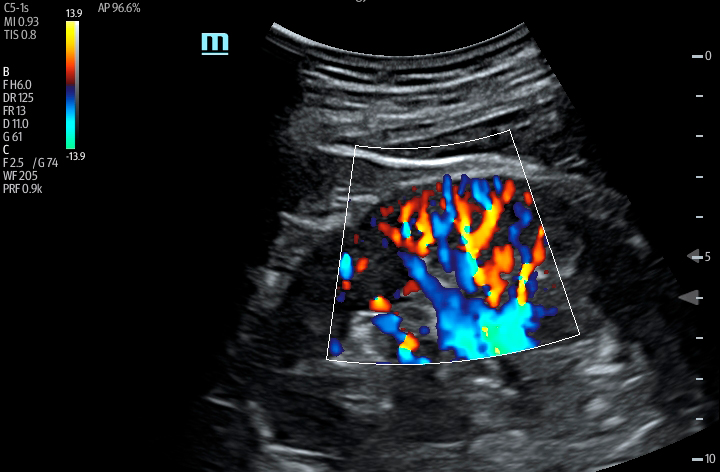

The TE7 Ultrasound System Crystal Series 2.0 is the system of choice from routine point-of-care exams to extreme situations when every second counts. With best-in-class image quality, a sleek form factor, and breakthrough needle visualization advancements, the TE7 System is designed to provide superior performance for rapid, confident exams and procedures in the fast paced, point of care environment.

Smart VTI

Automated measurement of the Velocity Time Integral (VTI) and Cardiac Output (CO), enables rapid assessment of cardiac function. This software automatically locates color box and Pulse Wave Doppler (PW) sample line in real time. A graph of parameter trends for CO, Stroke Volume (SV) and VTI is produced to guide decision-making.